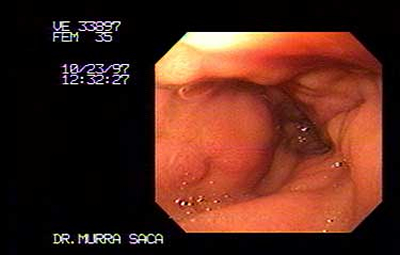

Paciente femenina de 35 años:

Consulta por dolor abdominal de dos meses de evolución, pérdida de peso e ictericia, vómitos de contenido alimenticio con fetidez. Dicha paciente había emigrado hacia los Estados Unidos de Norte América, en sus principios fue diagnosticada como Hepatitis viral A, manejada ambulatoriamente. Pero su cuadro empeoraba por lo que decidió regresar a su país de origen El Salvador.

-

Fotografía del caso anterior:

Carcinoma Gástrico que ha infiltrado toda la cámara gástrica, se observa el cardias por retroflexión el cual es infiltrado por dicho carcinoma parte negra es el Endoscopio.